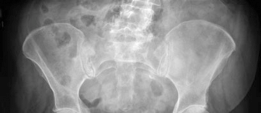

Standard antero-posterior and cross-table lateral radiographs of the pelvis and left hip were obtained immediately following the primary clinical assessment.

The initial AP pelvis radiograph clearly demonstrated a displaced left femoral neck fracture. The fracture line was entirely intracapsular. The femoral head was superiorly and posteriorly displaced relative to the femoral neck, with evidence of approximately 1.5 cm of shortening. The bone quality appeared reasonable for the patient's age, with a preserved Singh index and cortical thickness in the diaphyseal region, though some osteopenia was evident in the proximal trabecular patterns. No signs of pre-existing significant hip osteoarthritis (such as joint space narrowing, subchondral sclerosis, or osteophytosis) in the ipsilateral joint were noted. The contralateral hip appeared unremarkable.

Further radiographic views confirmed the complete displacement and the lack of cortical contact between the proximal and distal fragments. The fracture was classified as a Garden Type IV, indicating complete displacement with a loss of trabecular alignment between the femoral head and the acetabulum, where the head has rotated independently of the neck. Furthermore, it was classified as a Pauwels Type III, meaning the fracture line angle was greater than 70 degrees from the horizontal. This vertical fracture orientation indicates extremely high shear forces across the fracture site, portending a very poor prognosis for osteosynthesis and a high risk of nonunion or fixation failure if internal fixation were to be attempted.

Preoperative digital templating is a mandatory step in the surgical workflow for arthroplasty. Templating was performed on the AP pelvis radiograph, utilizing the contralateral, uninjured hip as a reference for restoring the center of rotation, femoral offset, and leg length. The templating process involves: